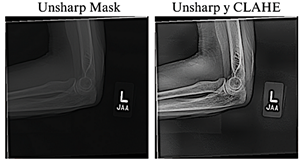

thorough analysis, four images in an incompatible format were identified and excluded in subsequent preprocessing stages, thereby confirming the total of 40,005 images reported by the authors [23]. The resulting 40,005 images were normalized and resized to 384 × 384 pixels to maintain a balance between preserving relevant details, ensuring computational efficiency, and achieving consistency with the pre-trained models. To improve the visual quality of the radiographs, the Unsharp Masking technique, used to emphasize edges and fine details [24], and CLAHE, which improves contrast in low-quality images without introducing unwanted artifacts [25], were applied. Previous studies have shown that combining these techniques significantly enhances visibility in low-light images [26], as illustrated in Figure 2.

Figure 2. Application of radiographic image enhancement techniques. The image on the left shows the result obtained using Unsharp Mask, while the image on the right illustrates the effect of combining Unsharp Mask with CLAHE.